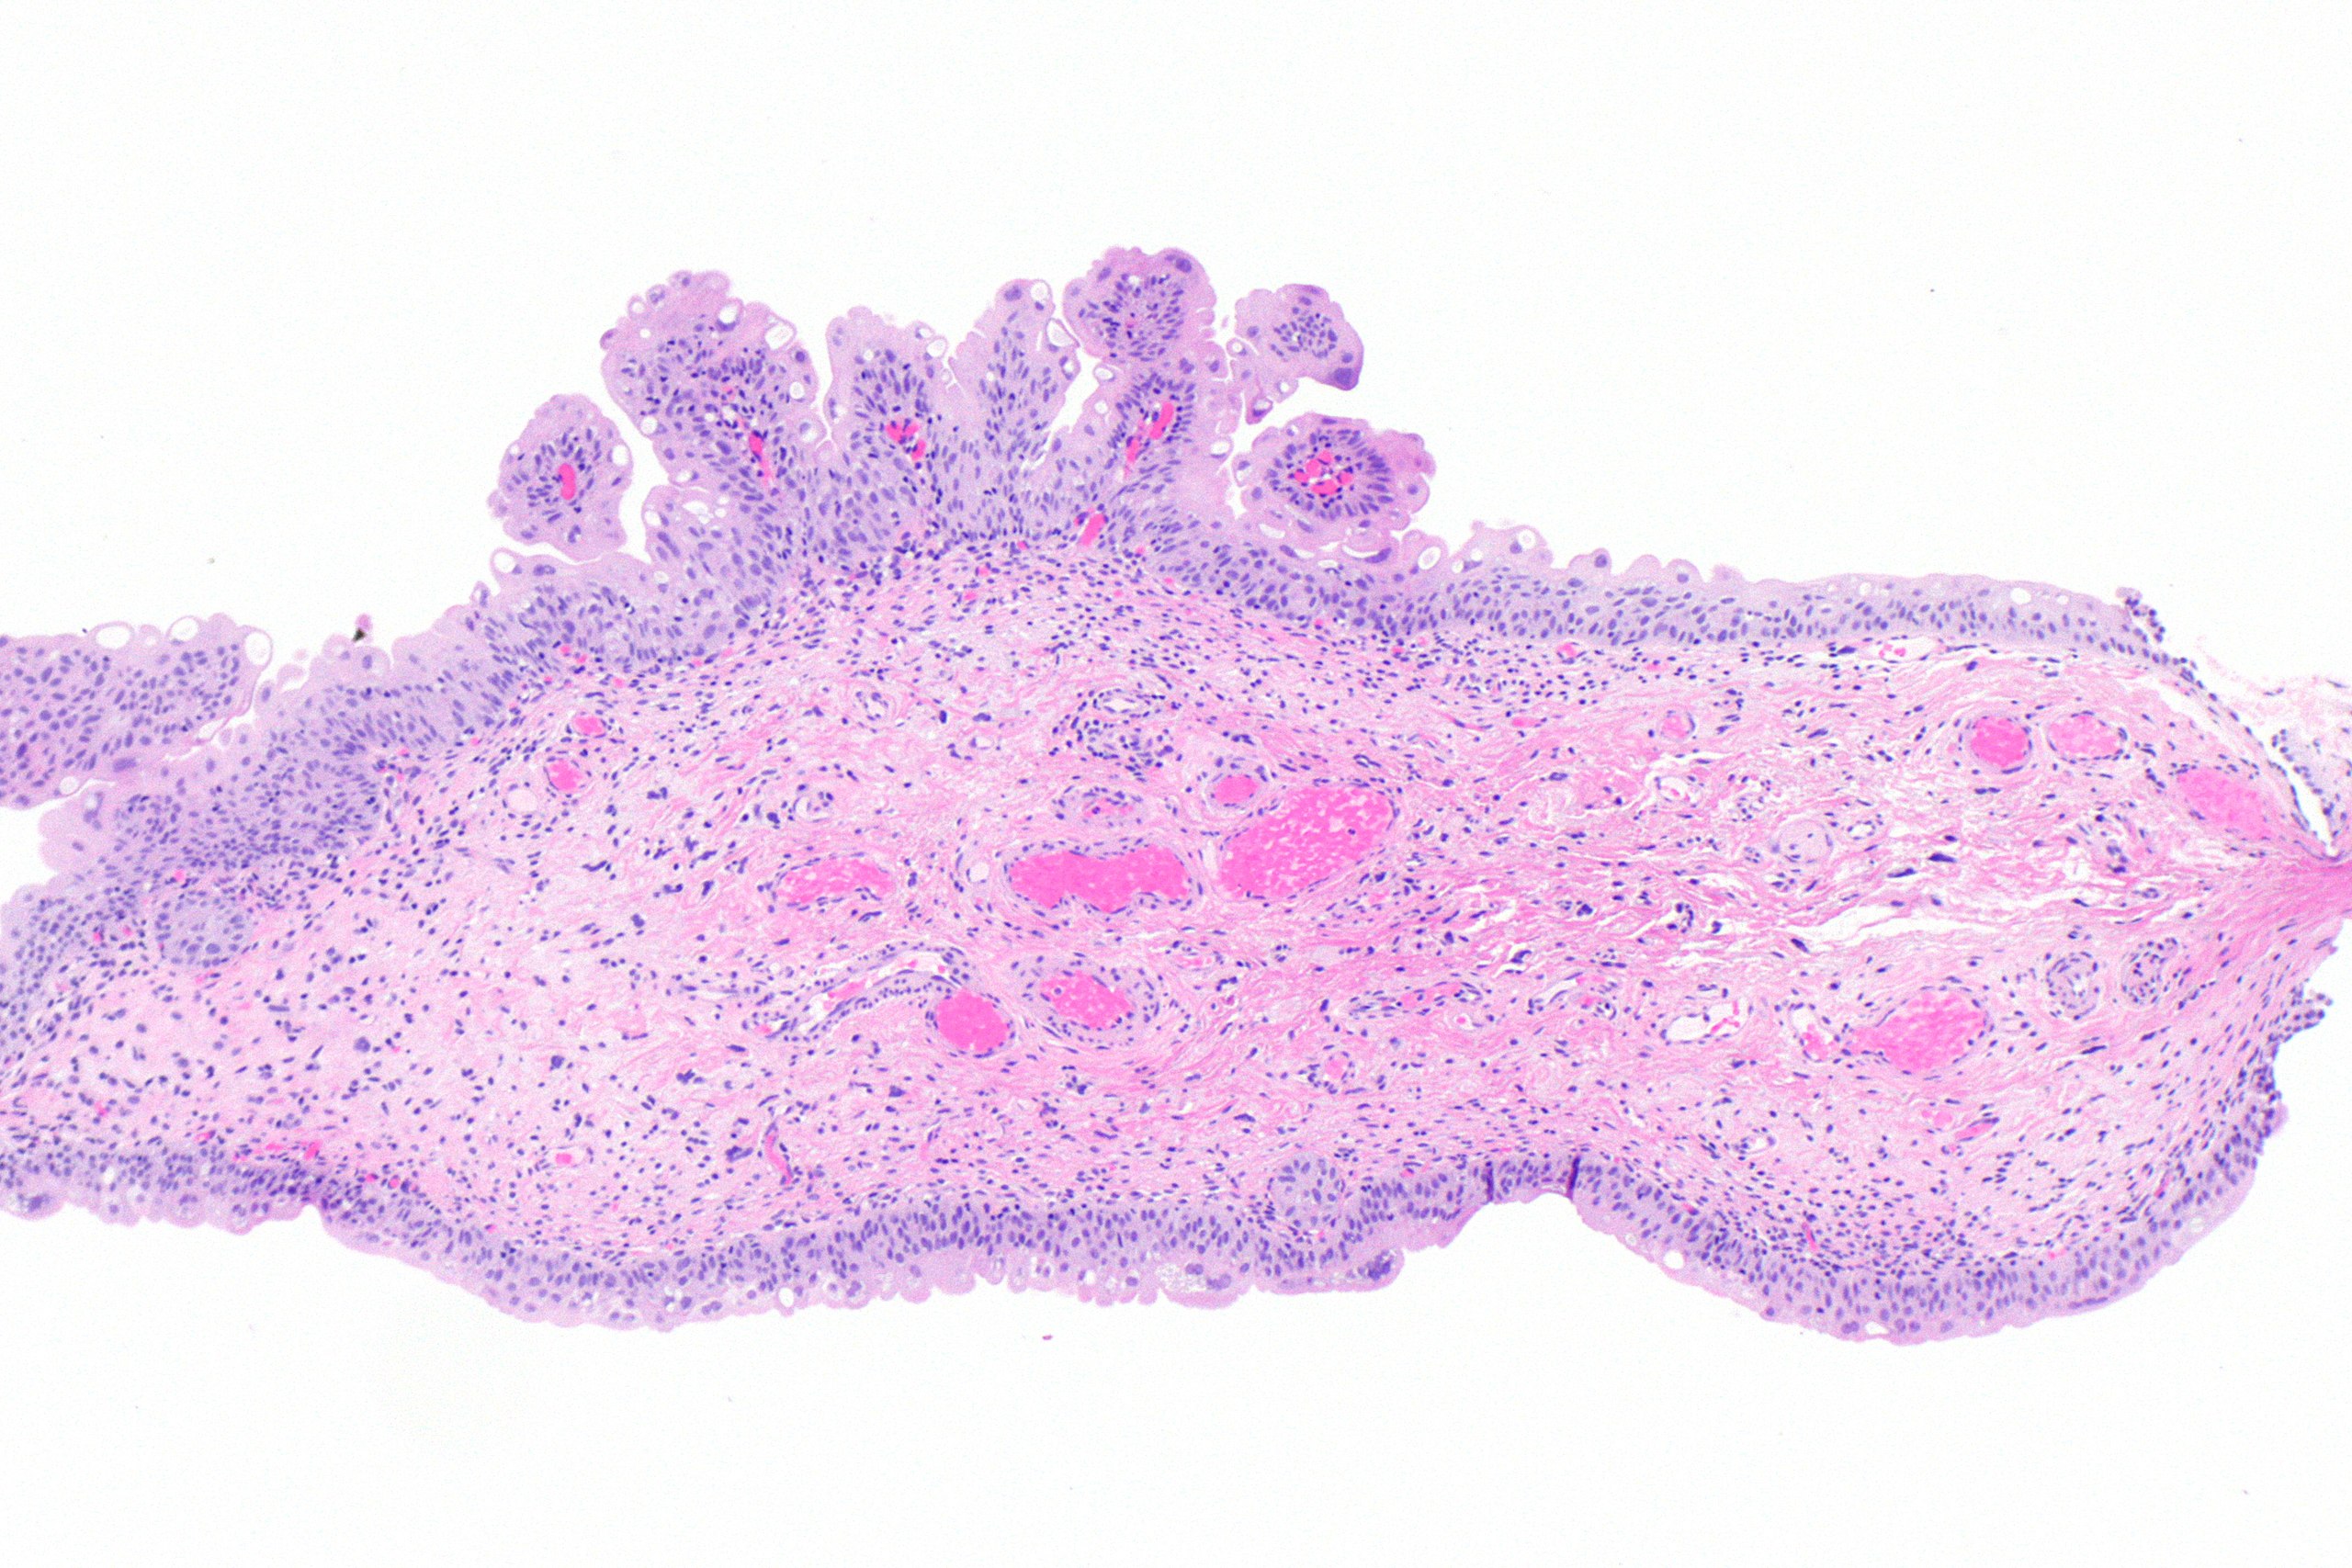

Papillomlar, üretelyum tabakasındaki hücrelerde iyi huylu anormal büyümedir. Büyüyen bu hücreler gerek mikroskopla bakıldığında gerekse çıplak gözle olarak parmaksı çıkıntılar oluşturur. Bu parmaksı çıkıntılar, bağ dokusu hücreleri, damarlar ve eoitel hücrelerinden oluşur.

- Papiller büyüme: Mikroskop altında parmak benzeri çıkıntılar (papiller) olarak görünür.

Papillomlar, genellikle sistoskopi ve biyopsi ile tanı konan bir hastalıktır. Sistoskopi sırasında mesanede veya ürotelyal epitel içeren diğer bölgelerde papiller yapılar gözlemlenir. Biyopsi alınarak, papiller dokunun mikroskopik incelemesi yapılır. Mikroskopik incelemede, papilla yapılarının düzgün sınırlı, ince ve anastomozlaşan trabeküler yapılar oluşturduğuna bakılır. Ürotelyal papillomun, inverted ürotelyal karsinom ve Von Brunn adalarından ayırt edilmesi önemlidir.